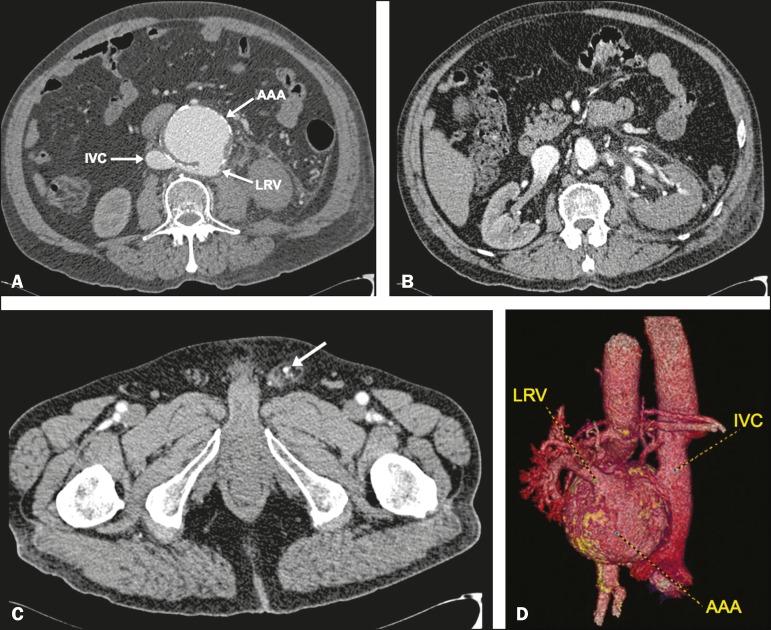

Fistula between the abdominal aorta and a retroaortic left renal vein: a rare complication of abdominal aortic aneurysm.

https://cdn.ncbi.nlm.nih.gov/pmc/blobs/82a5/5746888/11bd93b2dbdc/rb-50-06-0407-g01.jpg